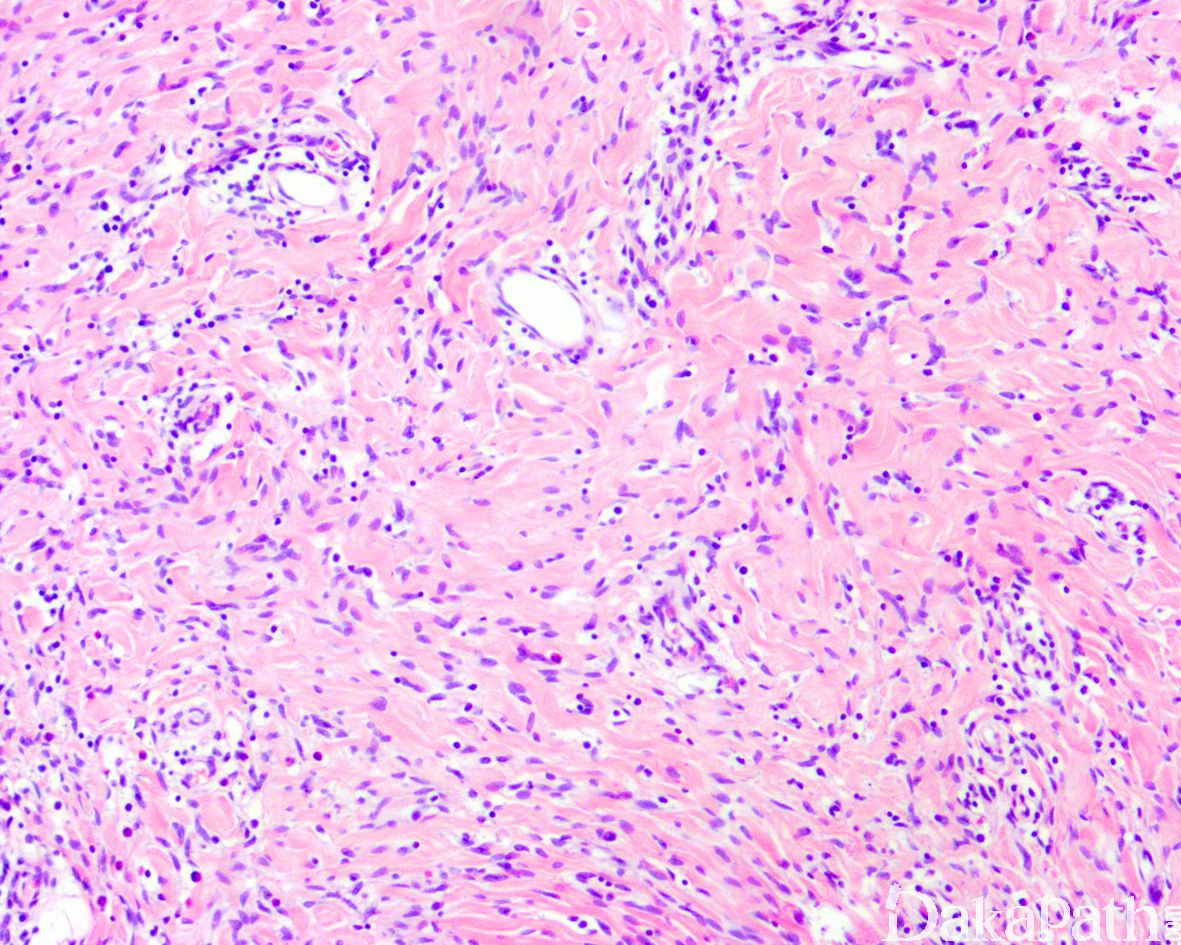

镜下位于真皮深层或皮下,边界不清;由致密梭形细胞、原始间叶细胞和成熟脂肪组织组成,不同病例三者比例不同:

致密的纤维组织由比较成熟的纤维母细胞、肌纤维母细胞和胶原纤维组成,呈纵横交错的束状排列,常呈指状伸入脂肪组织内,组织学类似于纤维瘤病;部分区域可见梭形细胞之间成片的胶原化或瘢痕化以及多核巨细胞沉积,类似于乳腺的假血管瘤样增生或巨细胞纤维母细胞瘤样改变;

原始间叶组织呈结节状分布,由幼稚的短梭形、卵圆形或星状细胞排列成呈疏松的漩涡状、巢状或宽带状包被于富于血管的黏液性基质之间;

瘤细胞形态均教温和,核异型性轻微,罕见核分裂象;